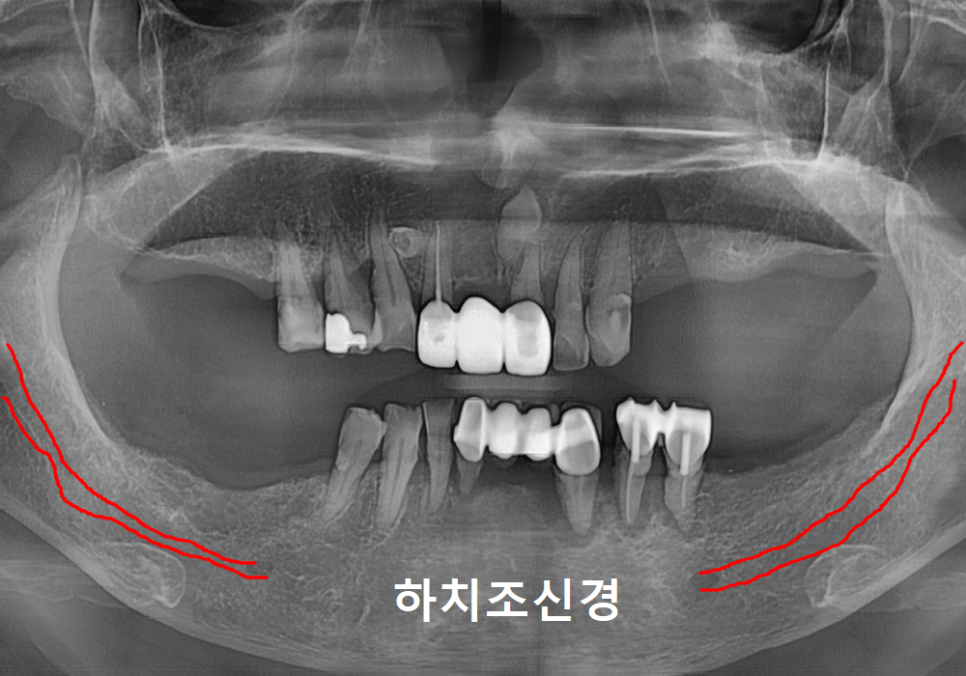

이 환자분 케이스에서 가장 중요했던 점은

아래턱을 지나는 하치조 신경을

완벽히 피하는 것인데요.

만약 임플란트가 이 신경을 조금이라도 건드리면

안면 마비나 감각 이상 같은

심각한 부작용이 생길 수 있기 때문에

주의해야 하는 구조물 중 하나입니다.

일반적인 방식이었다면

의사의 감각에 의존해 신경관과의 거리를

가늠하며 조심스럽게 심었겠지만...